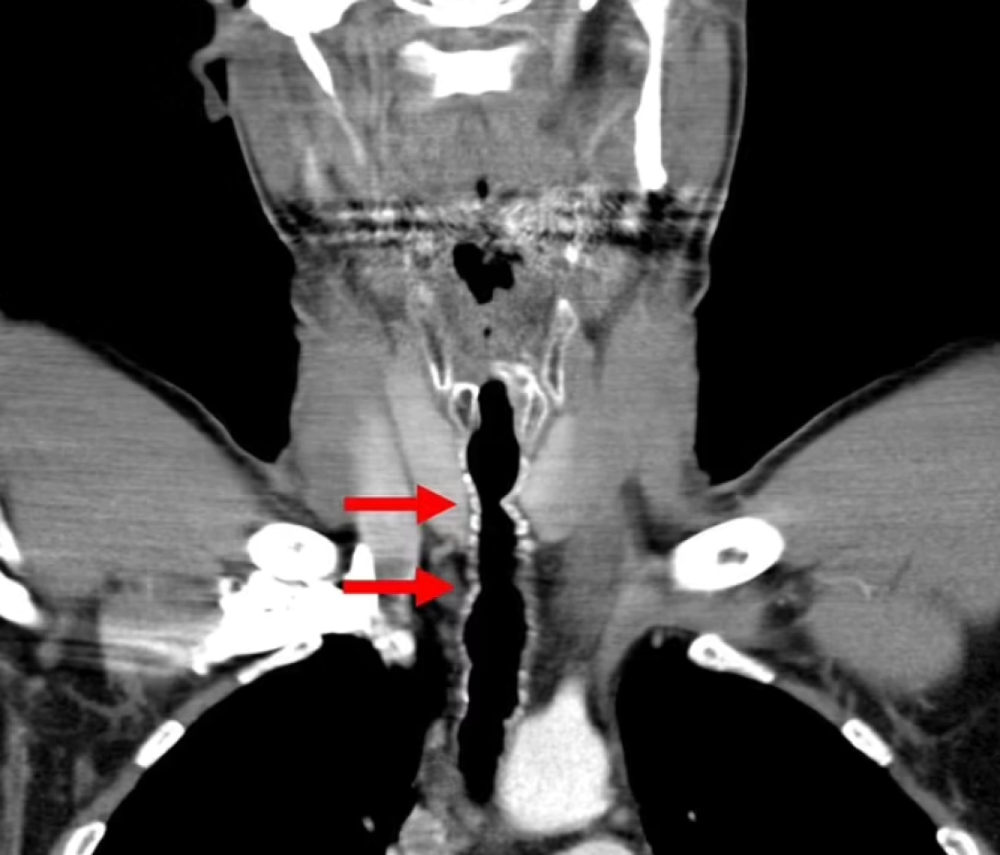

Пацієнт звернувся до лікарів зі скаргами на хрипкий голос, утруднене дихання та хронічний кашель. Його одразу відправили на спеціальну процедуру, щоб провести маленьку камеру дихальними шляхами. Таким чином вдалося виявити кілька волосків, які росли з тієї ділянки горла, де чоловікові колись робили операцію (пересаджували шкіру з вуха).

Волосся видалили, але вони й надалі продовжували відростати, тому австрієць щоразу повторно звертався по допомогу протягом багатьох років. Розлад вдалося вилікувати тільки після того, як він кинув палити і зважився на ендоскопічну аргоноплазмову коагуляцію — спалювання кореня, з якого росте волосся.